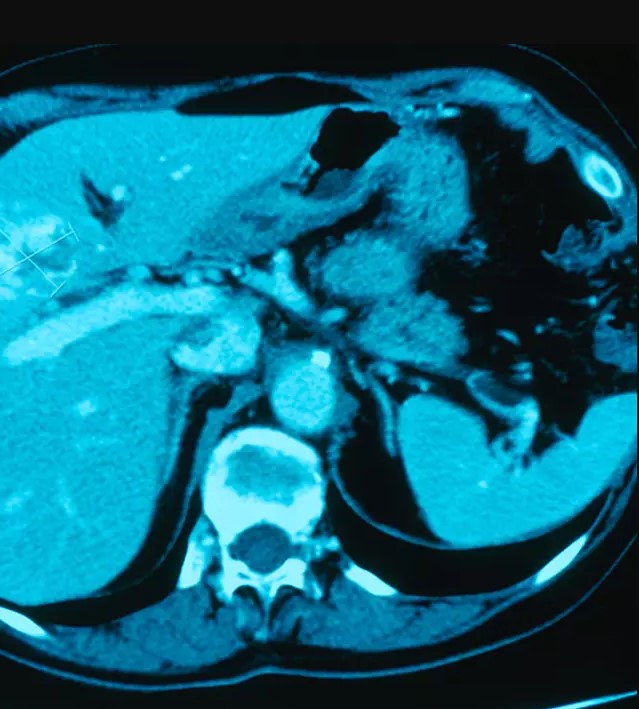

不過koi pla所使用的魚類體內常有寄生蟲,若是處理不當吃下肚,寄生蟲便會潛入人體膽管,最終引發癌症,泰國每年約有2萬人因此患病死亡。

肝臟外科醫生Narong Khuntikeo以切身之痛透露,他的父母就是因為這道料理喪命,而肝臟癌症又被稱為「沈默的殺手」,Narong醫師直言「這對健康造成很嚴重的問題,但沒有人知道這一點,因為他們靜靜死去,就像樹葉從樹上掉下來一樣」。目前醫界和科學界專家已經合作對伊桑省居民進行寄生蟲檢測,並宣導koi pla的危險性,希望能從根本改善民眾的飲食問題。